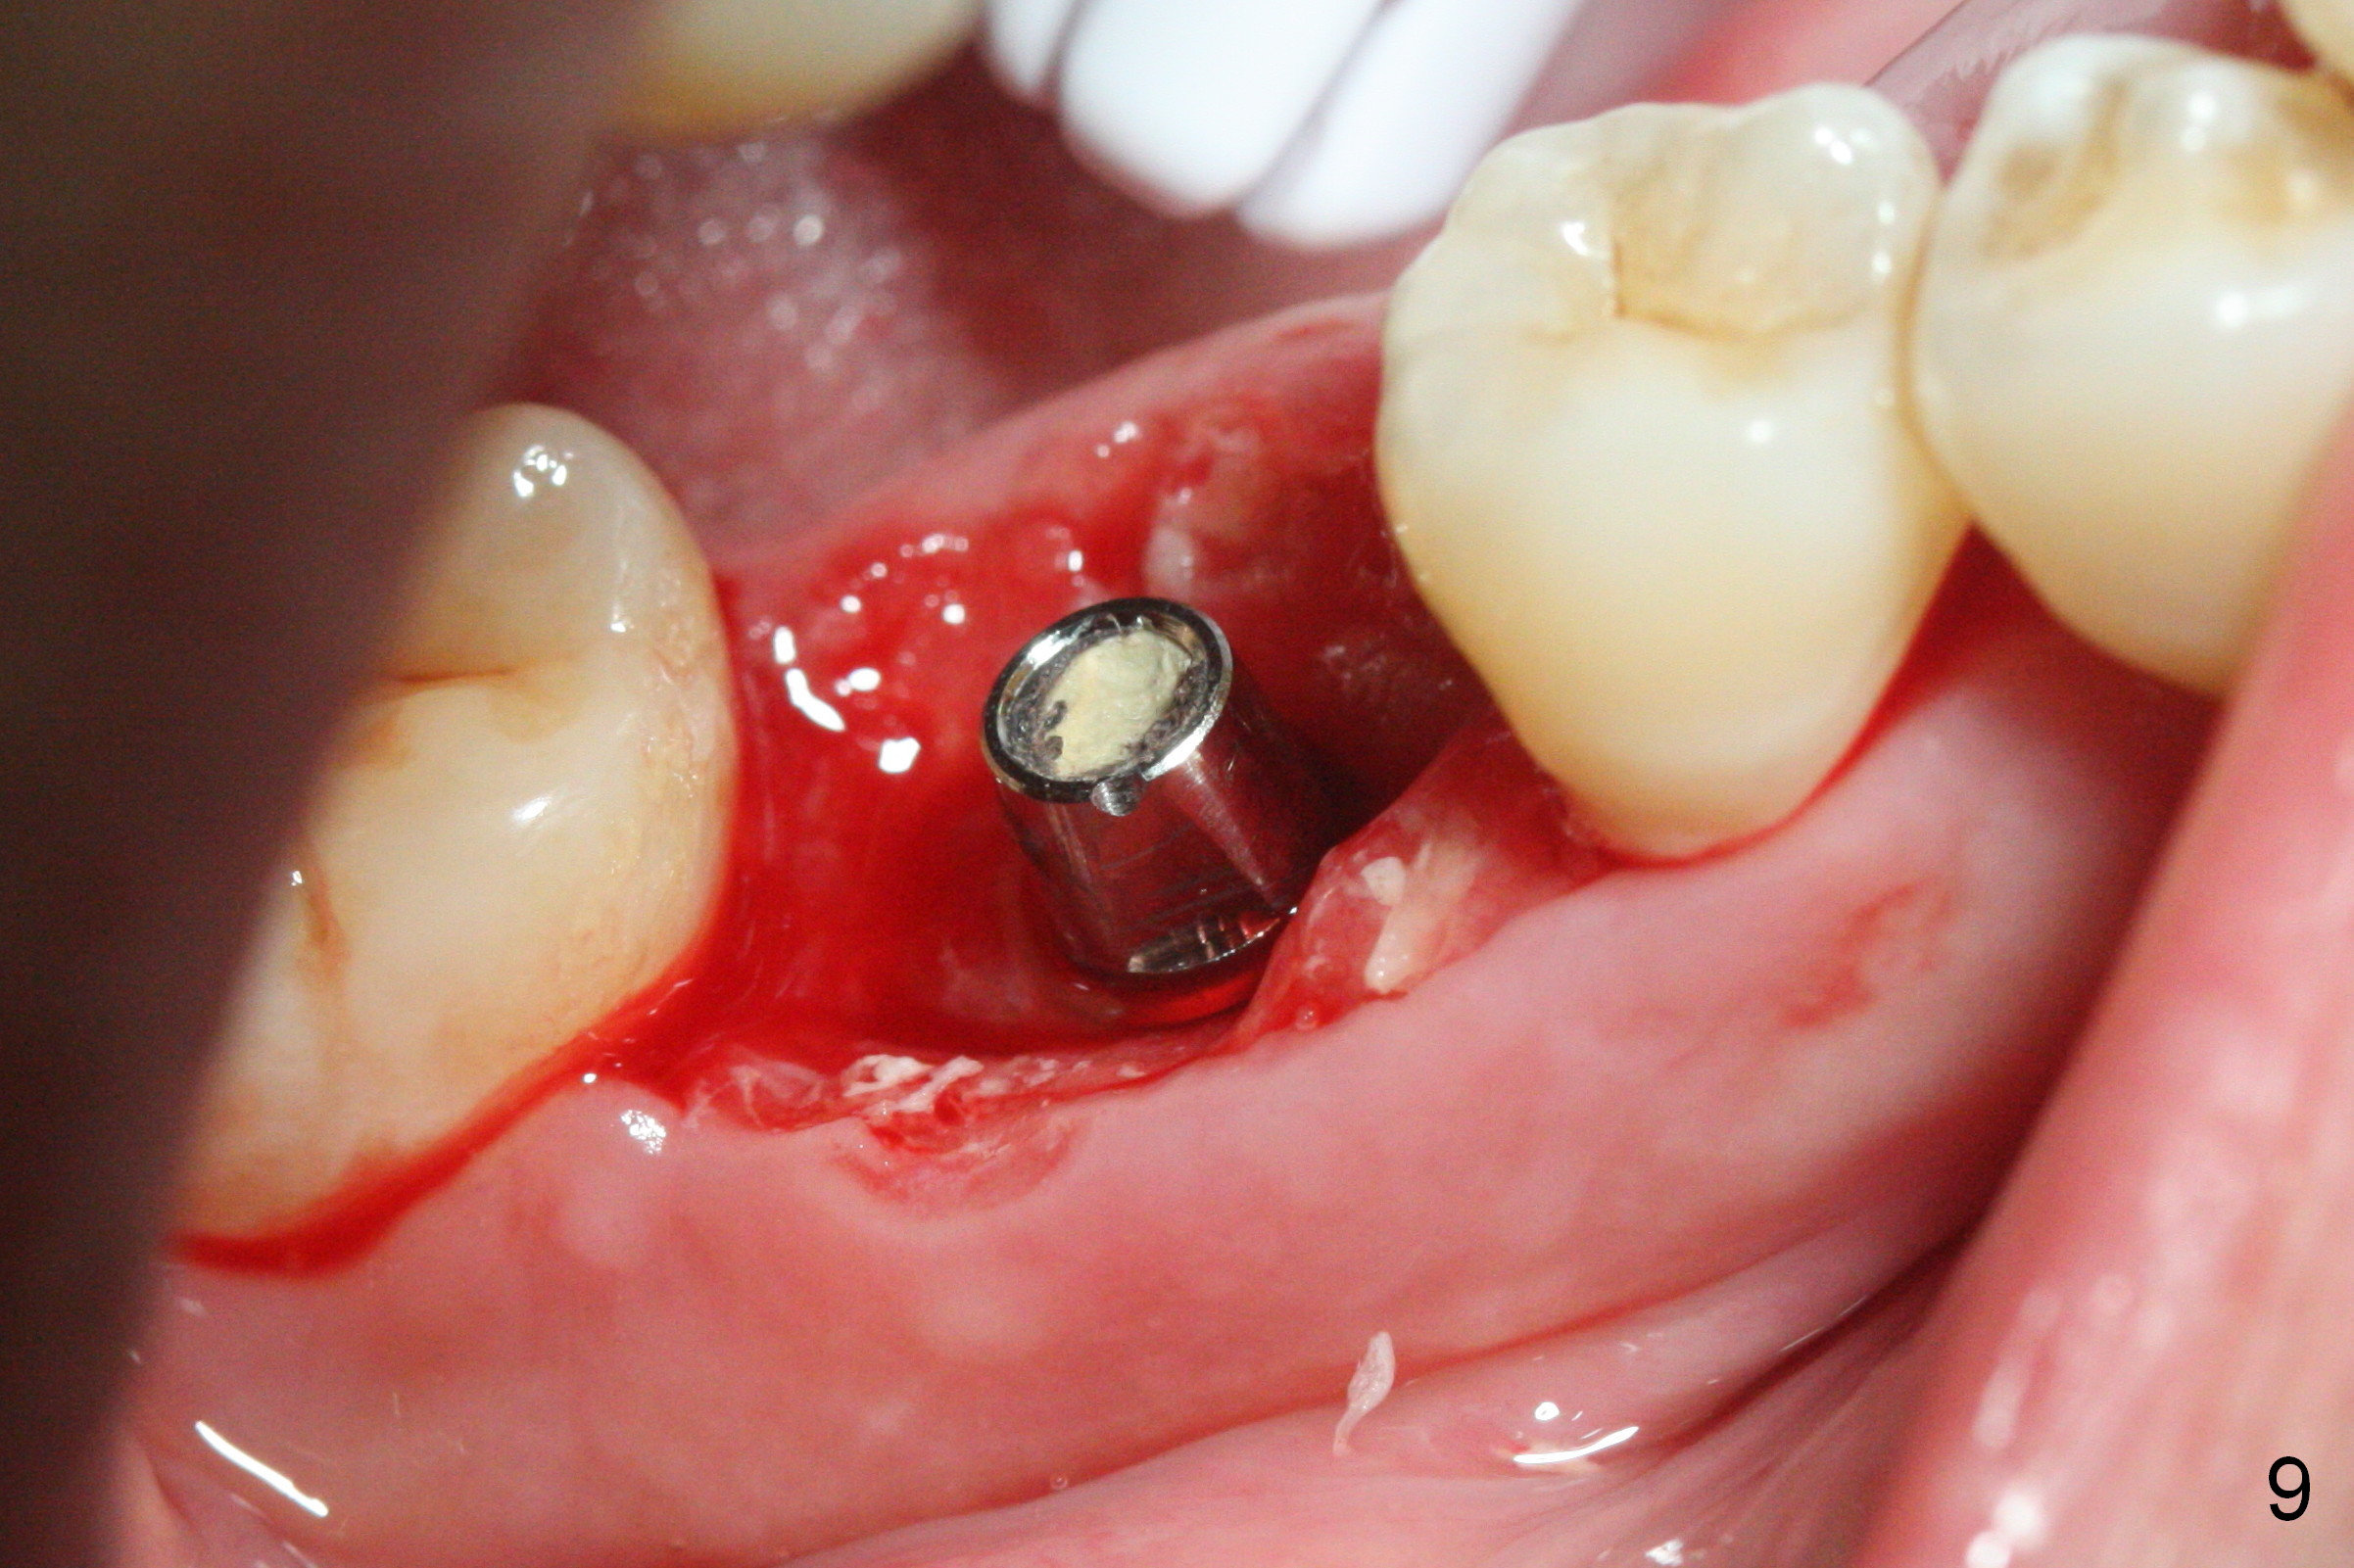

The patient returns 5.5 months postop for final restoration. The implant appears to have osteointegrated (Fig.8). When the locked in provisional is removed, the gingiva bleeds (Fig.9). She will return in 2 weeks. The abutment remains incompletely seated nearly 2 years post cementation (Fig.10).